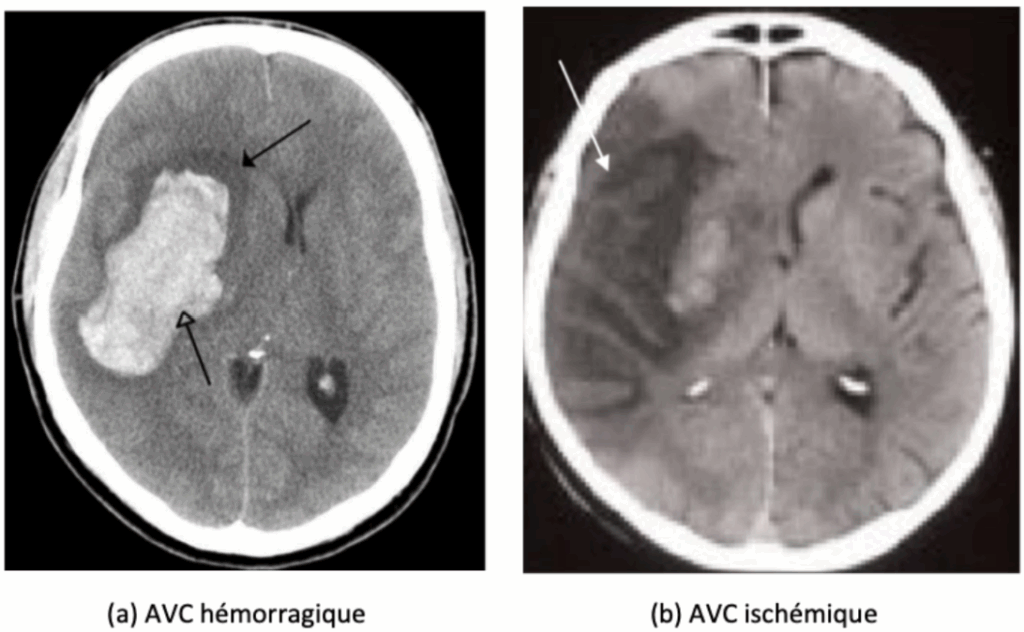

Lorsqu’un AVC est suspecté, le premier examen réalisé est généralement un scanner cérébral sans injection (tomodensitométrie - TDM) [23], lorsque l’Imagerie à Résonance Magnétique (IRM) n’est pas possible. Rapide et largement accessible, il permet avant tout de détecter une éventuelle hémorragie intracrânienne, qui apparaît sous forme d’une zone hyperdense (blanche) comme le montre la Figure 3.

Figure 3 : Aspect au scanner des AVC ischémique et hémorragique (Source : Léa PIETERS, Université de Lille 2, 2017) [24]

Si une hémorragie est mise en évidence, le diagnostic d’AVC hémorragique est posé et une prise en charge spécifique est initiée. Si aucun saignement n’est visible, l’hypothèse d’un AVC ischémique aigu est privilégiée. Dans ce cas, une angiographie par scanner (angio-TDM) peut être réalisée pour visualiser les artères cérébrales et repérer une occlusion d’un gros vaisseau (Figure 4).